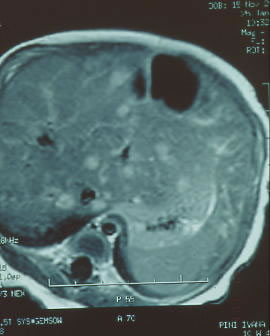

Emangiomatosi multipla neonatale Figure 3 b

Emangiomatosi epatica associata |